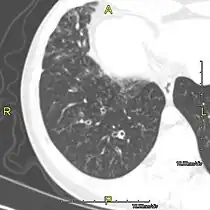

Sagittal CT image showing "tree in bud" appearance of mucous impaction in distal small airways related to primary ciliary dyskinesia -

CT image showing dilated and thickened medium-sized airways (bronchiectasis) in a patient with Kartagener syndrome -